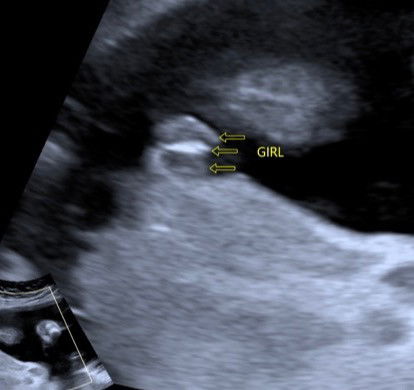

confirm girl tak

hi mommies. macam ni confirm girl tak? mommy dia dah excited kalau dia girl sebab dah ada sorang boy. tapi takut juga dia scam🤣🤣🤣